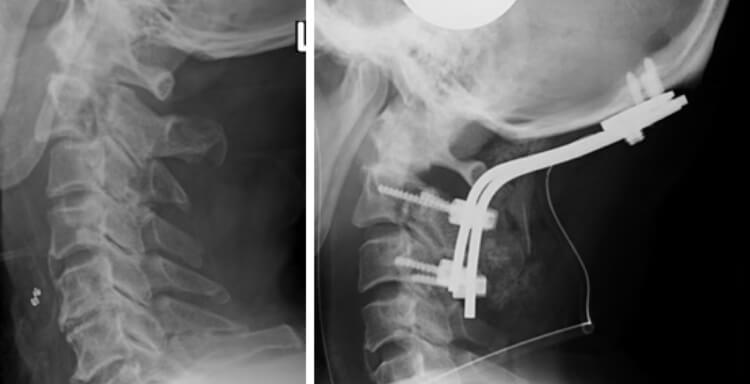

頚椎頸髄損傷症例

転倒による第2頚椎骨折の症例。骨折により頚椎が亜脱臼しており、後頭頚椎固定を行いました。